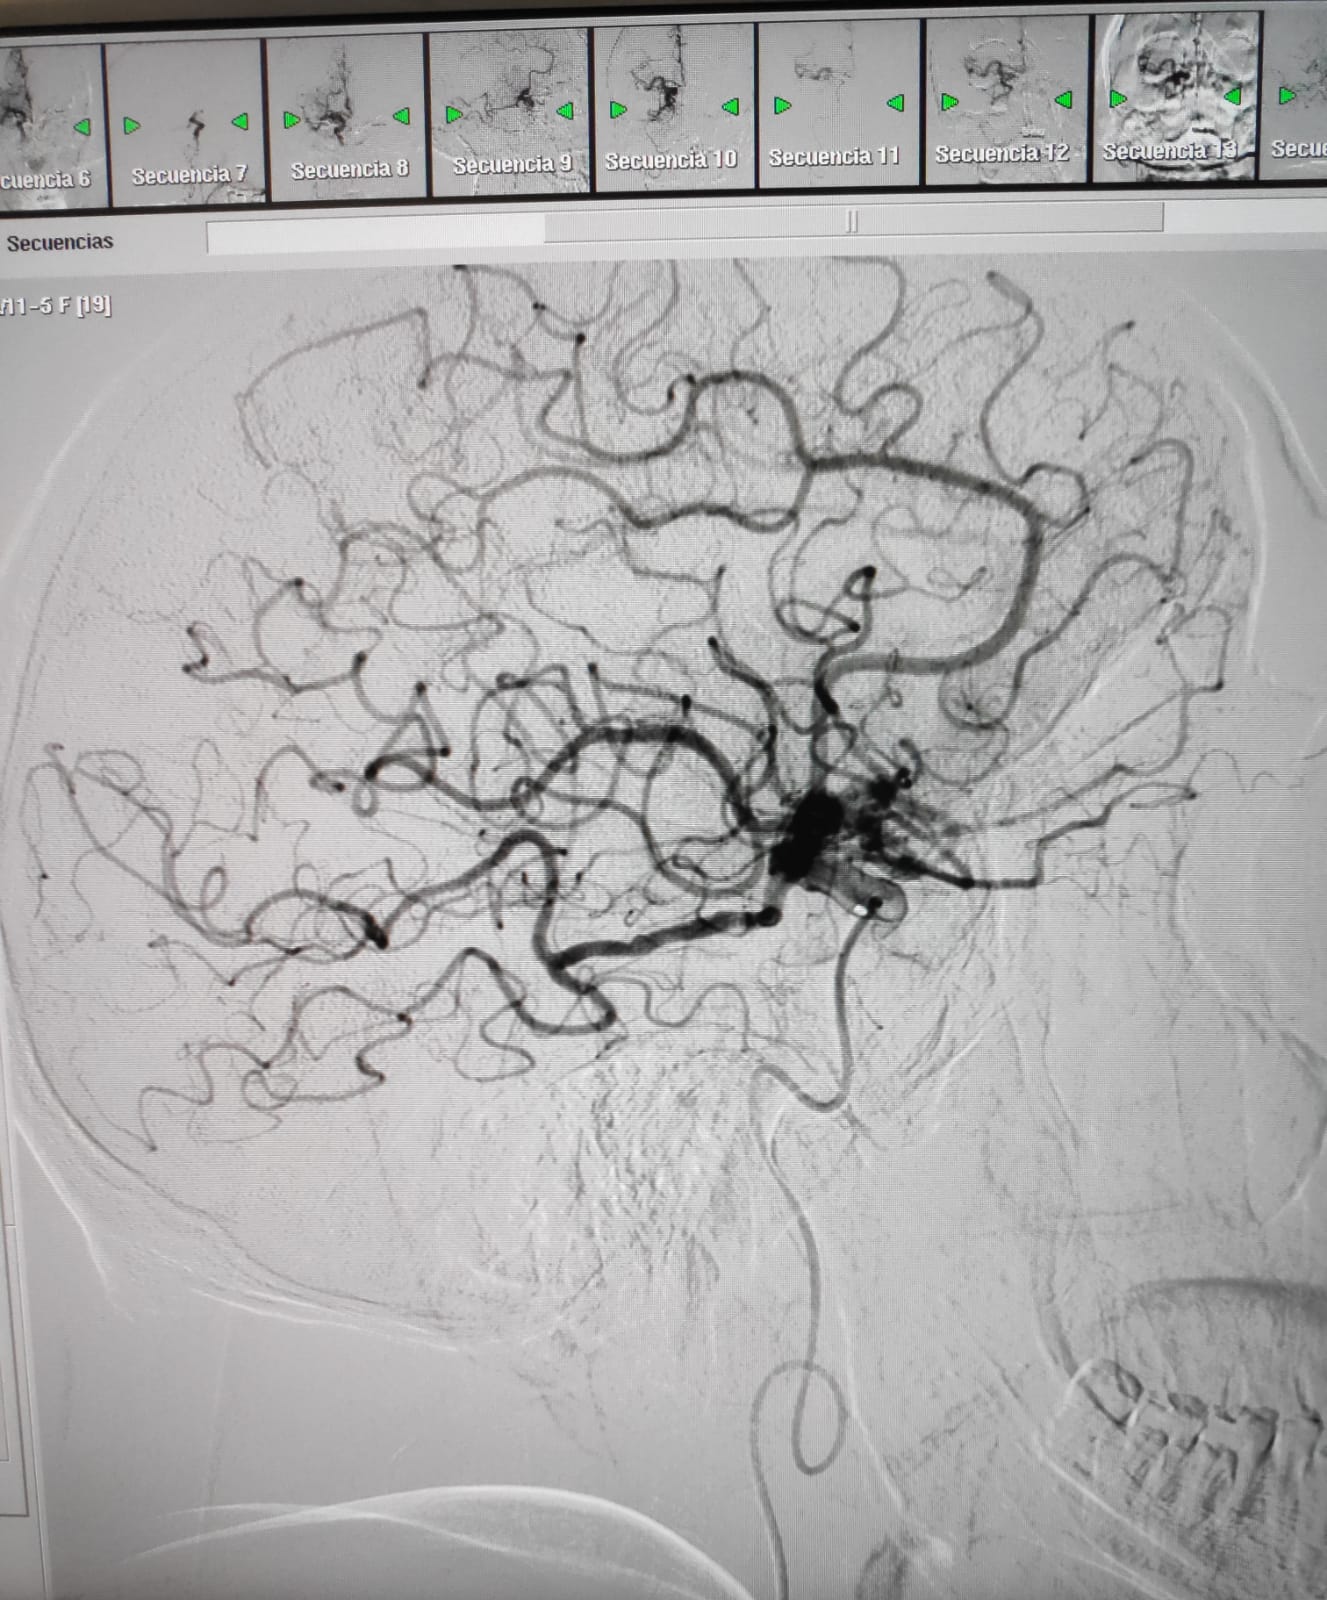

En aquestes dues imatges, podem veure com queda afectada la circulació arterial arran d'un ictis isquèmic i com es recupera després del tractament endovascular.